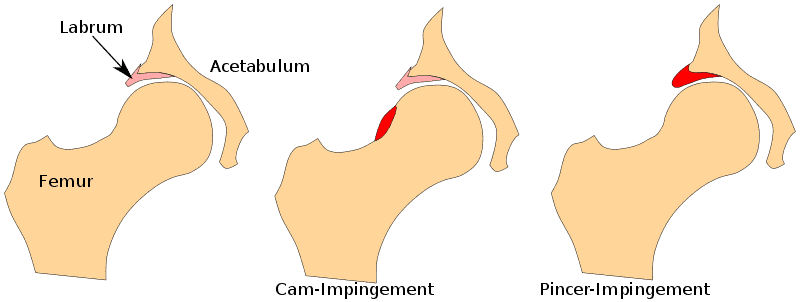

Femoroacetabuläres Impingement (FAI), auch Hüftimpingement genannt, bezeichnet morphologische Veränderungen der Hüftpfanne und/oder des Oberschenkelhalses, die bei Bewegungen zu einem Aufprall auf die Hüftlippe führen. Wir können zwischen zwei Haupttypen unterscheiden: Wenn der Hüftkopf zu groß ist, spricht man von einer CAM-Morphologie (die bei Männern häufiger vorkommt), und ein überstehender Hüftpfannenrand wird als Zangenmorphologie bezeichnet und ist häufiger bei Frauen zu finden. Bei einem gemischten Typ sind sowohl eine CAM- als auch eine Pincer-Morphologie vorhanden.

Pathomechanismus

Es wird angenommen, dass sich diese Morphologie als spezifische Anpassung an die Anforderungen während der Adoleszenz entwickelt. Es könnte sein, dass sich die Wachstumsplatte verschiebt, wodurch der Kopf weniger rund, aber größer wird. Sobald sich die Wachstumsfugen schließen, ändert sich die Morphologie nicht mehr. Die Morphologie des FAI ist bei asymptomatischen Menschen und sogar bei 50-70 % der Sportler häufig. Viele Menschen haben also Anomalien, aber nur ein kleiner Teil entwickelt Schmerzen.